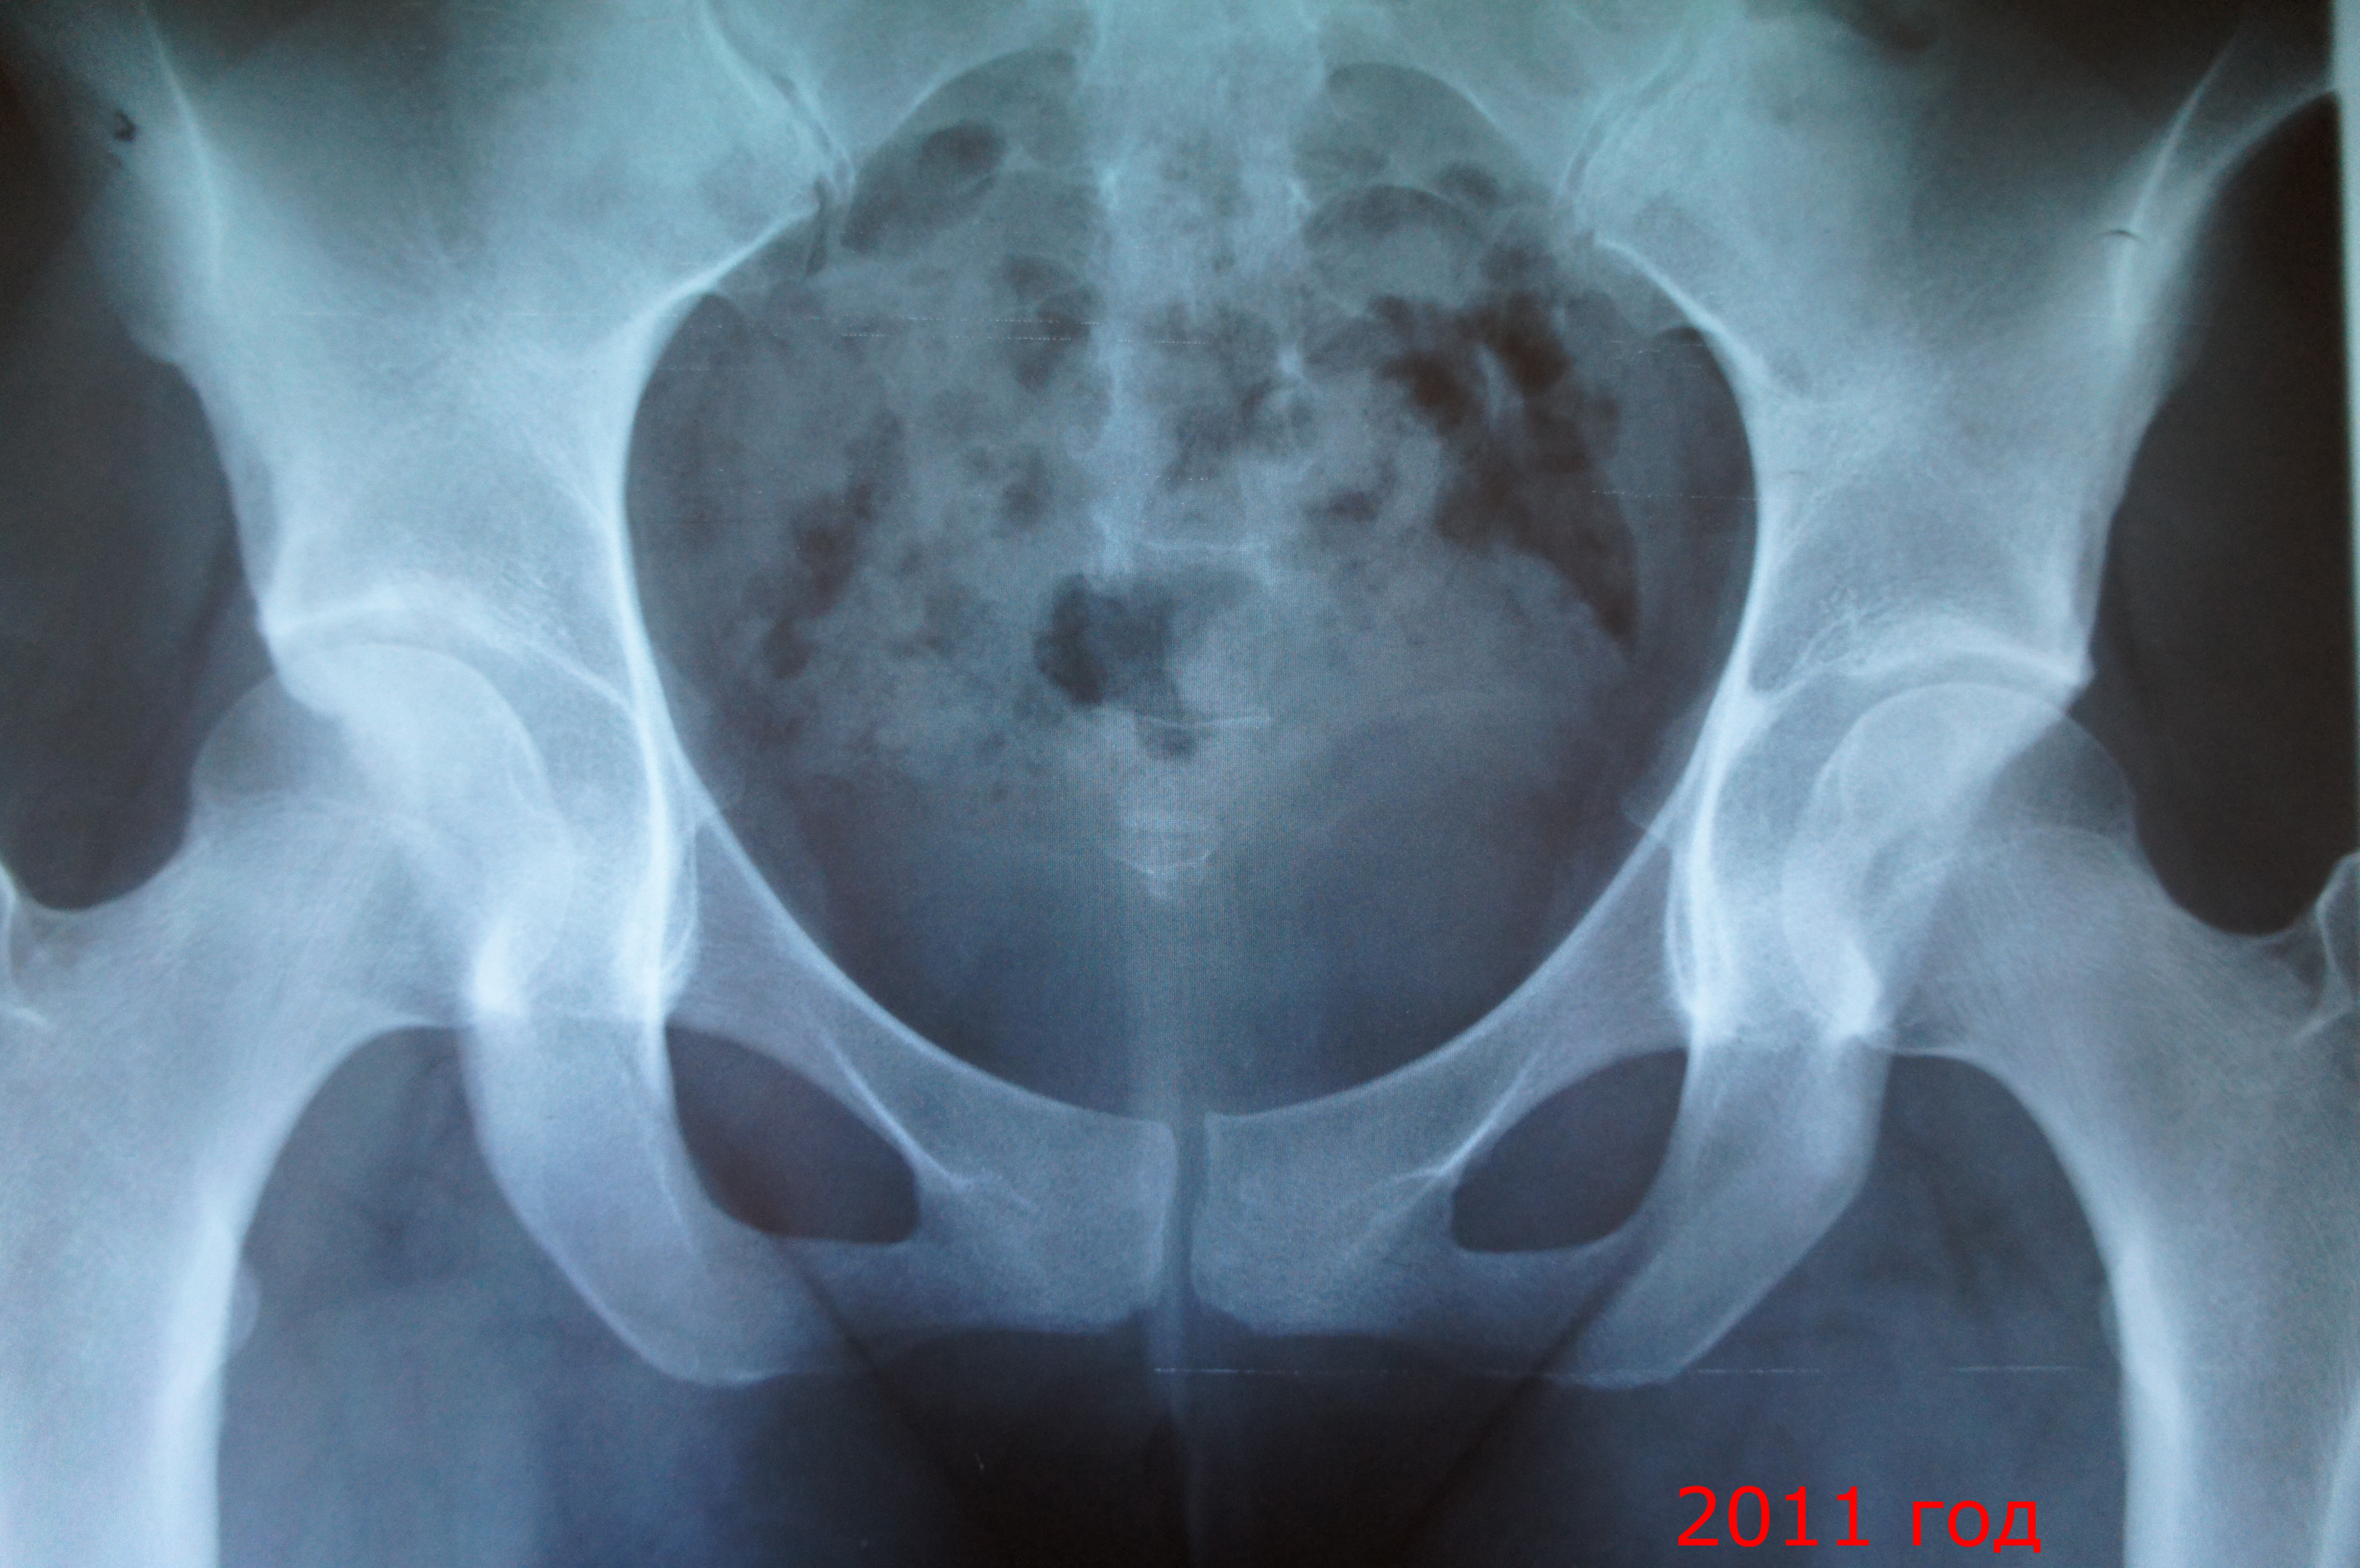

Прошу помочь в уточнении диагноза, так как за 6 лет слышала их много. Выкладываю снимки суставов в динамике с 2008 по 2012г.

Ходить начала в 8 мес., тогда очень искривились ноги, потом до 3 лет выпрямились. С 12 до 17 лет занималась спортивной аэробикой (2-4 раза в неделю, участвовала в соревнованиях). Суставы никогда не беспокоили, кроме как громкого хруста в таз.суставах на упражнении "велосипед лежа". Однажды на одной из тренировок заболел правый сустав, но я продолжила активно заниматься. После этой тренировки на утро долго не могла согнуть ногу в суставе, была сильная боль. Травматолог сначала поставил диагноз "растяжение", но так как боль не прекращалась, пошла к другому врачу-хирургу, тот впервые поставил диагноз "дисплазия". Рекомендовал полностью отказаться от тренировок. Физиотерапия, массаж и уколы хондропротекторов убрали основную боль. Через год заболел и левый сустав. Боль несколько изменила характер: стали мучать ноющие боли при лежании на твердом, при смене погоды, при долгой ходьбе и ходьбе на каблуках. Ревматолог не подтвердил проблем по его части. Очередной врач поставил диагноз в 2009г. - двусторонний коксоартроз 1 ст. Каждый сезон пила хондропротекторы, проходила физлечение. Сейчас боли возникают четко при вышеупомянутых причинах (ходьба и т.д.). Месяц назад хирург по снимкам сказал, что вообще никаких отклонений в суставах не видит, лечение против артроза прекратить, в спорт.нагрузках неограничены. А боль-то осталась, хоть и терпимая и предсказуемая. Движение в правом суставе немного ограничены при отклонении вперед, также имеется продольно-поперечное пплоскостопие.

Вероятно, дисплазии и артроза и динамики нет. Уточнить двигательную активность может только врач курирующий Вас. Заочно это сделать очень трудно. Мы не видим ситуацию в целом. Рекомендую в момент наличия болей посетить также невропатолога. Может быть они не связаны с суставами.

Дисплазию не сбрасывал бы со счетов. Неполное покрытие головок, больше справа, вполне себе есть.

Согласен, вертлужные впадины мелковаты, но, вероятно, дисплазии нет. Смотрите схему и рентгенограмма с осевыми. Тип А - норма.